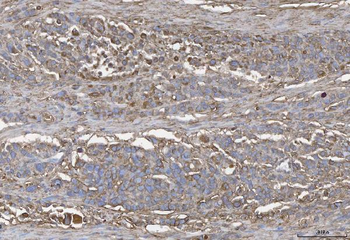

- Anti-GSTM3 Antibody [orb402287]

ELISA, IHC, WB

Human, Mouse, Rat

Rabbit

Polyclonal

Unconjugated

10 μg, 100 μg - Anti-S100 alpha 6/S100A6 Antibody [orb315184]